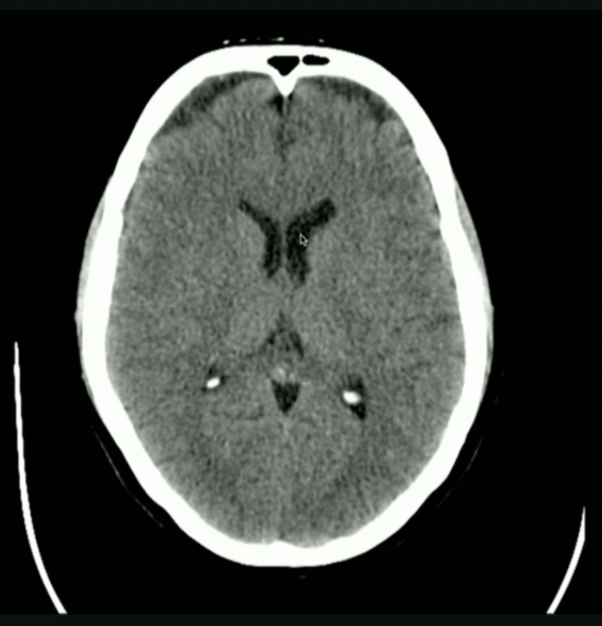

<p>Is this normal/abnormal?</p>

Is this normal/abnormal?

• Normal: the Choroid Plexus can Naturally Calcify